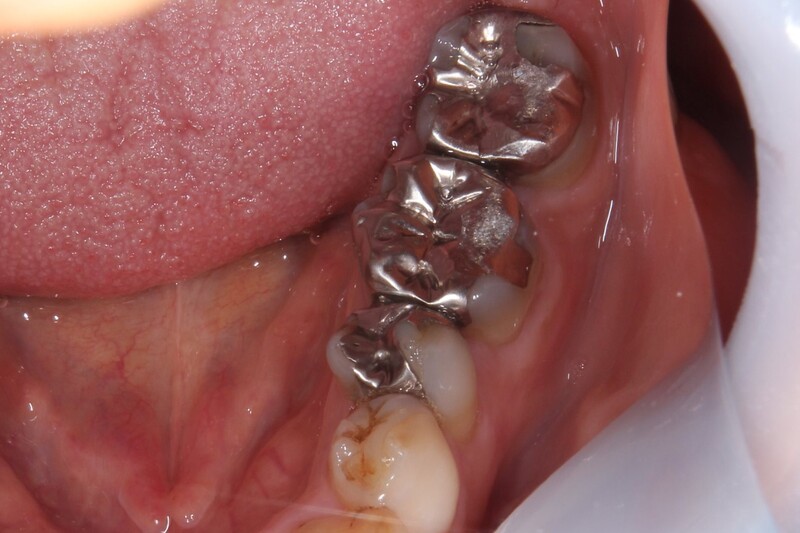

| 主訴 | 左下クラウンやり替えご希望 |

| 治療内容 |

左下6銀歯を除去 ジルコニアクラウンをセット |

| 治療費 | ジルコニアクラウン 55,000円 |

| 治療期間 | 2回 |

| リスク・副作用 | 硬い材料のため、歯ぎしりなど強い方は上の歯が削れたり負担になる可能性がある。 |